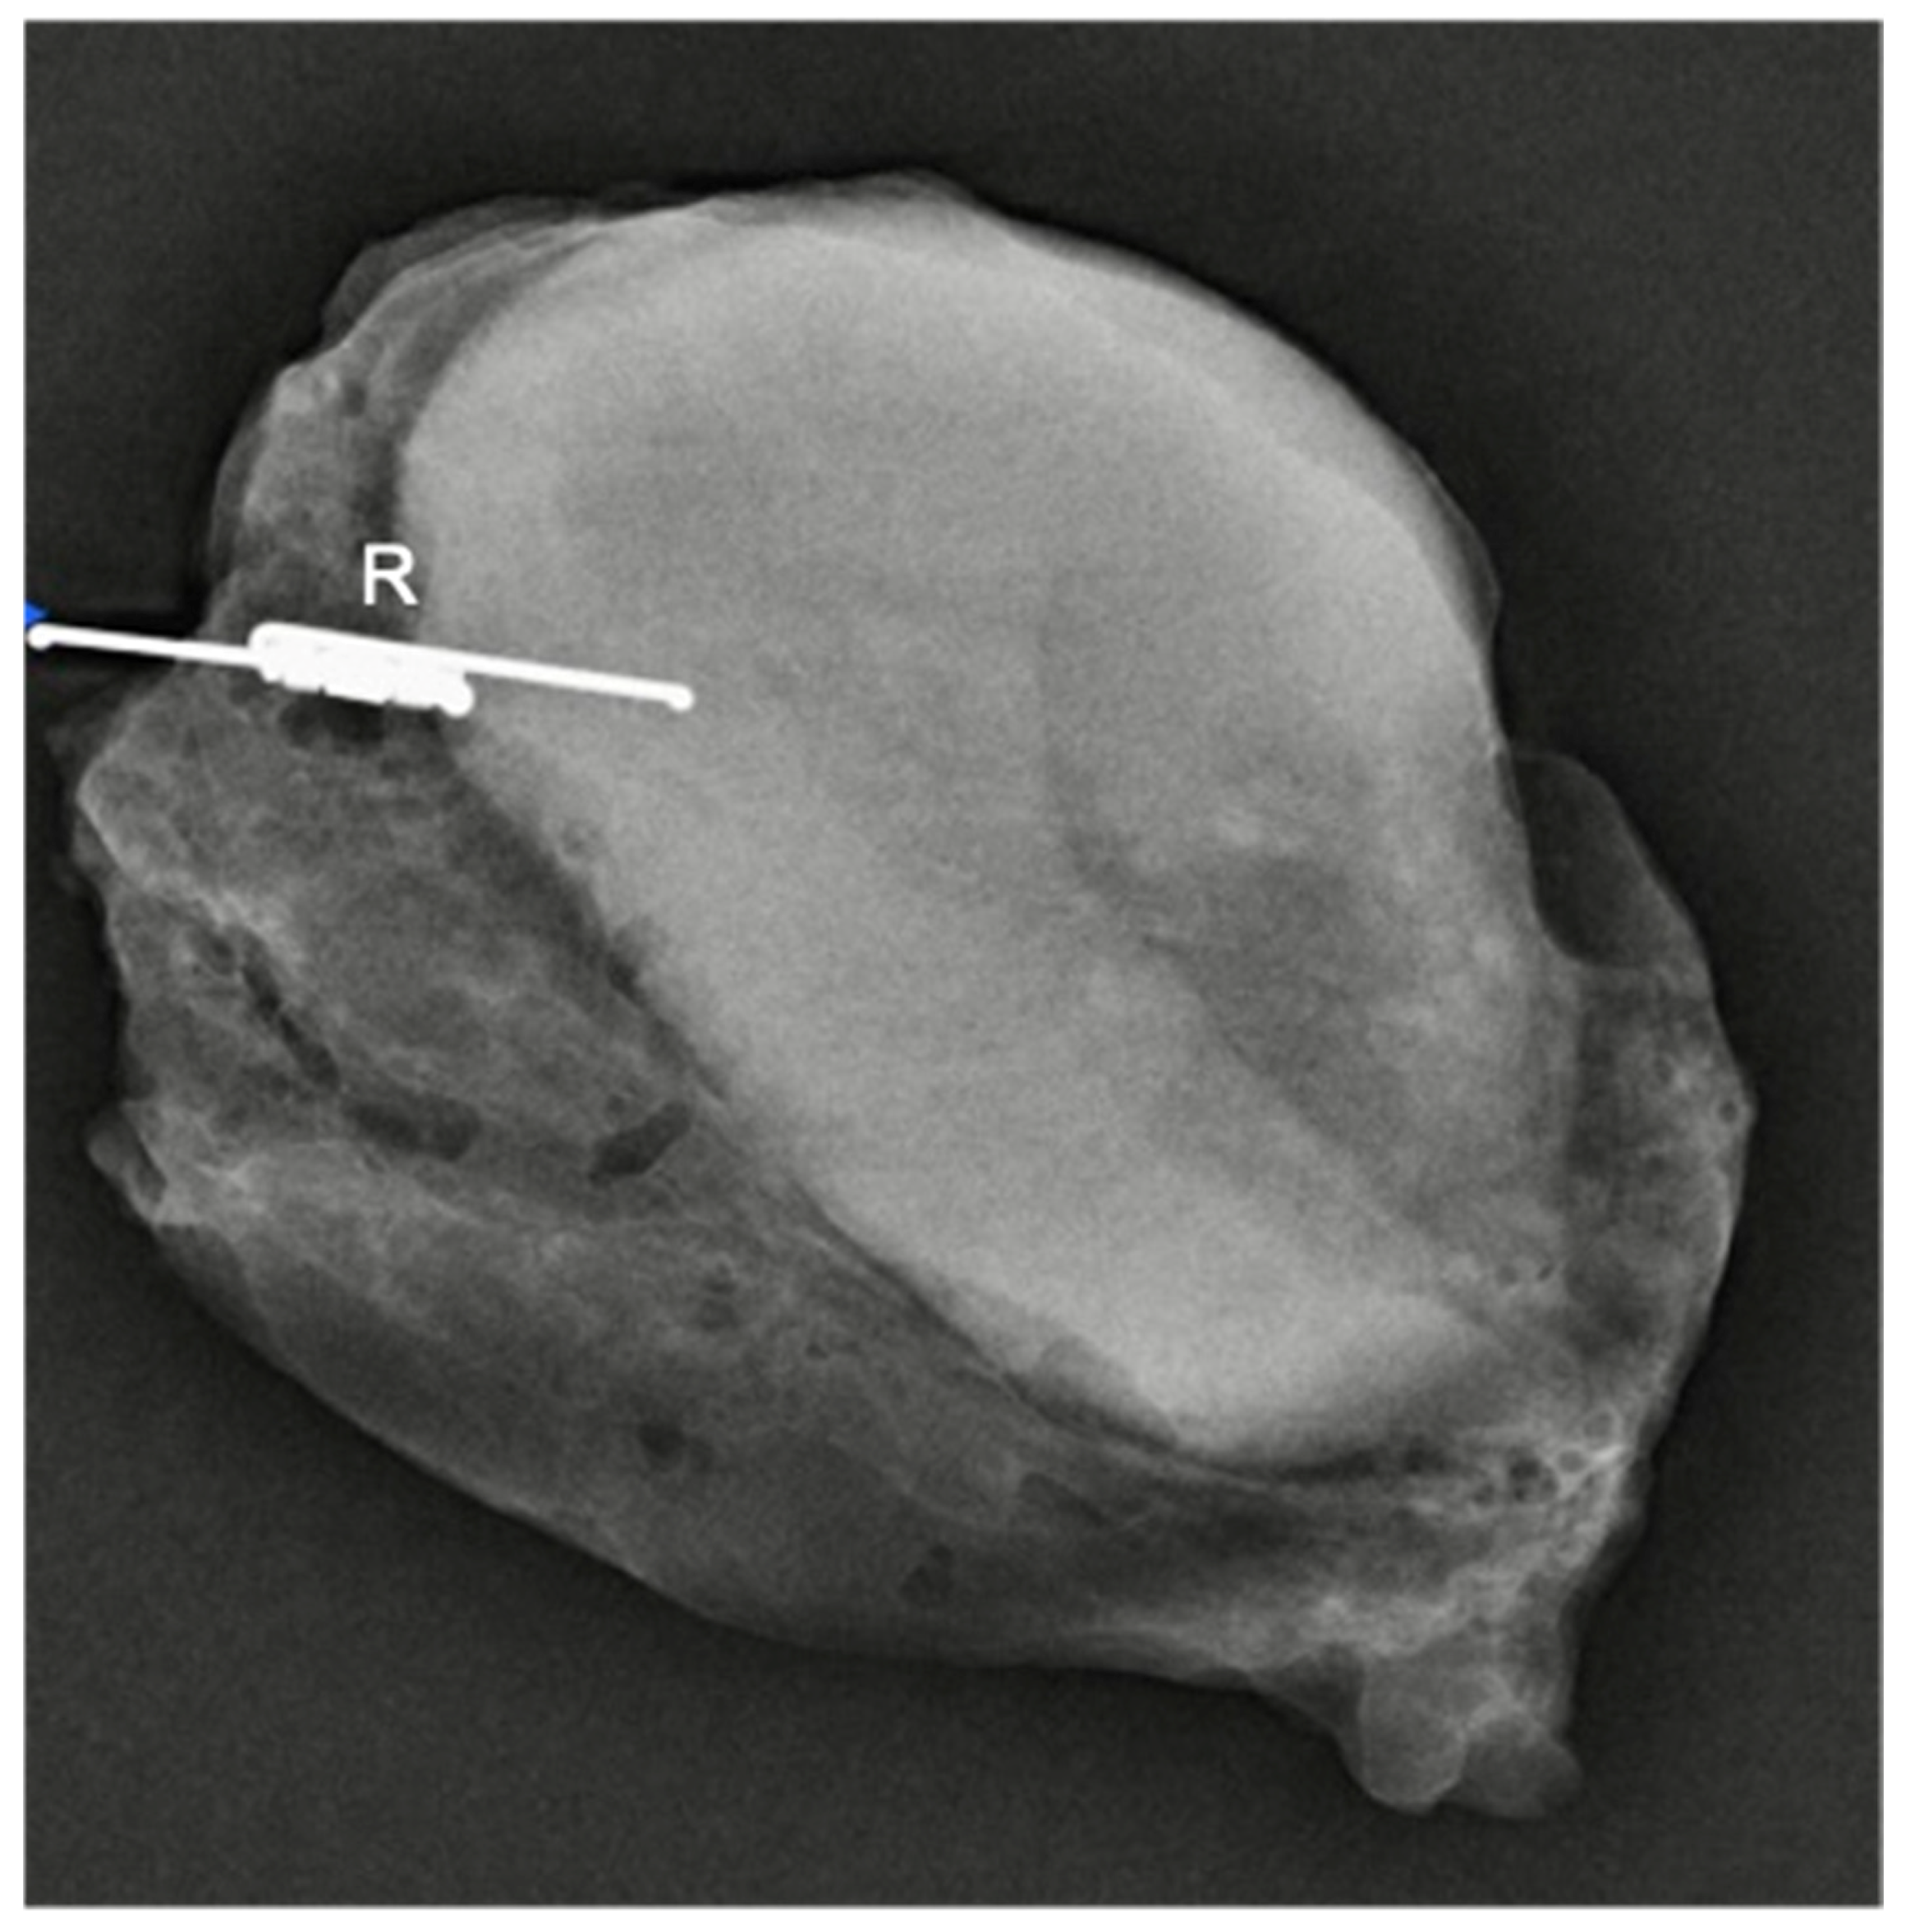

- Tayeh, S.; Muktar, S.; Heeney, J.; Michell, M.J.; Perry, N.; Suaris, T.; Evans, D.; Malhotra, A.; Mokbel, K. Reflector-guided localization of non-palpable breast lesions: The first reported european evaluation of the savi scout(r) system. Anticancer Res. 2020, 40, 3915–3924. [Google Scholar] [CrossRef] [PubMed]